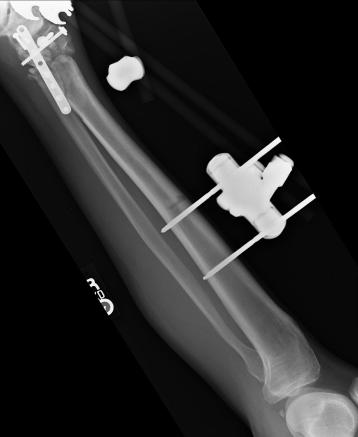

Post-corrective surgery X-Rays of the damaged right & left legs / ankles

The first two x-rays show Liam’s left ankle and pelvis prior to the accident. For comparison purposes it is interesting to see the

differences. The next x-rays were taken after the corrective surgery performed by Dr. Armendariz. Noticed that Dr. Armendariz has used tibia

bracing and also aligned the bone fragments of the left leg so that they could heal in the proper orientation. The external fixation has been

removed and Liam’s left foot has been returned to a more natural alignment.